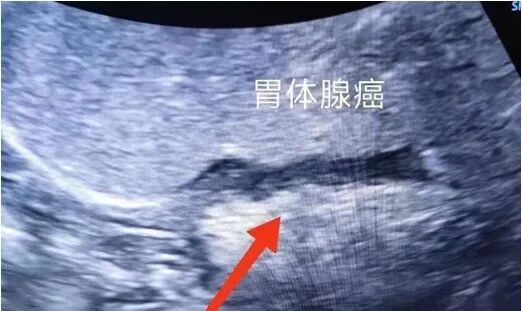

1、胃器质性病变:胃炎、胃溃疡、胃癌、胃间质瘤、胃壁异位胰腺、胃底静脉曲张、食管裂孔疝、贲门失弛缓症、十二指肠憩室等。